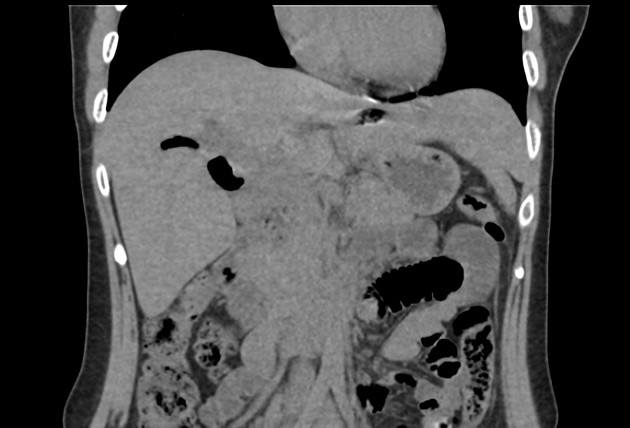

Khí đường mật

» Thông tin: Nữ giới – 30 tuổi.

» Lâm sàng: Đau mạn sườn phải / Tiền sử cắt túi mật.